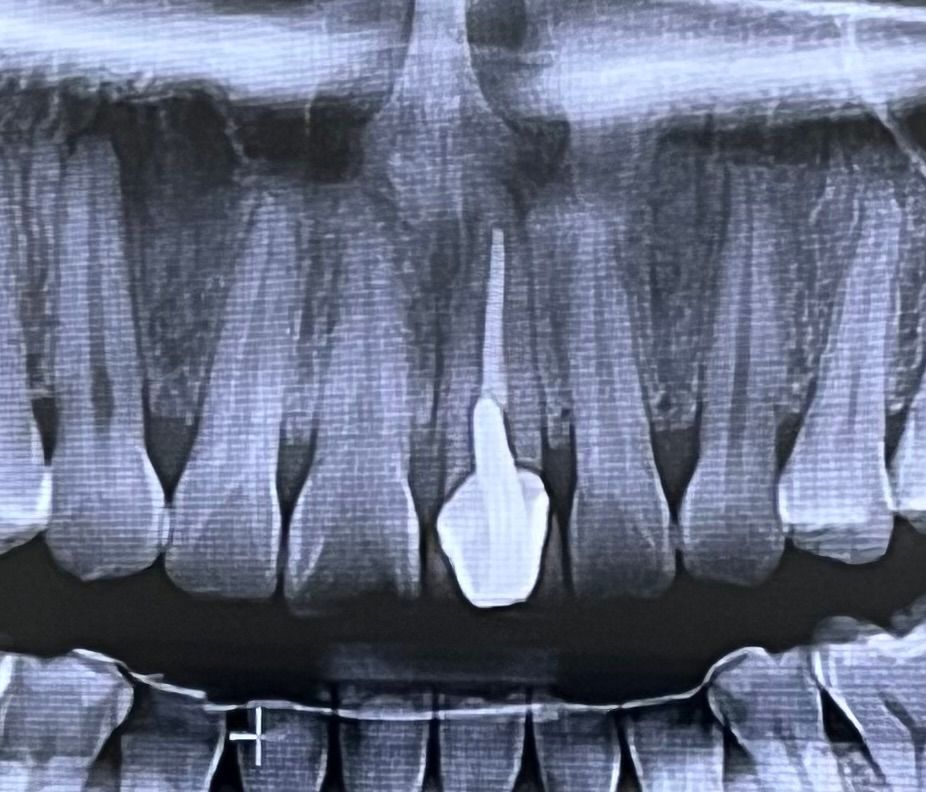

올해 초에 병원1에서 치아검진했을 때는

약간의 충치만 있고 지켜보잔 소견을 받았는데

최근에 사랑니 발치를 위해 방문한 병원2에서는 크라운한 치아 위쪽에 염증이 큰 범위로 있다하시네요 ㅠㅠ 발치에 대한 두려움으로 경황스러워

2. 앞니 크라운한 치아의 뿌리 주변 염증 상태는 파노라마 방사선 사진 말고 작은 치근단 방사선 사진으로 봐야 정확하게 진단이 가능합니다.

3. 염증(낭)이 치아 뿌리로 크게 잡힌 경우라도 통증이나 별다른 증상은 없을 수도 있습니다.

4. 처음에 신경치료를 한 원인이 치아 속 신경에 염증이 있어서 그랬던 거라면 염증이나 신경일부가 잔존해서 지속적으로 염증반응을 일으키고 뼈까지 염증이 진행된 상태일 수도 있습니다.

엑스레이 상으로 신경치료하신 치아 뿌리끝에 염증이 잇어 보지만 진행되는건 아니니 크게 문제가 잇는건 아닙니다. 정기적으로 사진을 찍어보시면서 관리하시면될것같습니다.